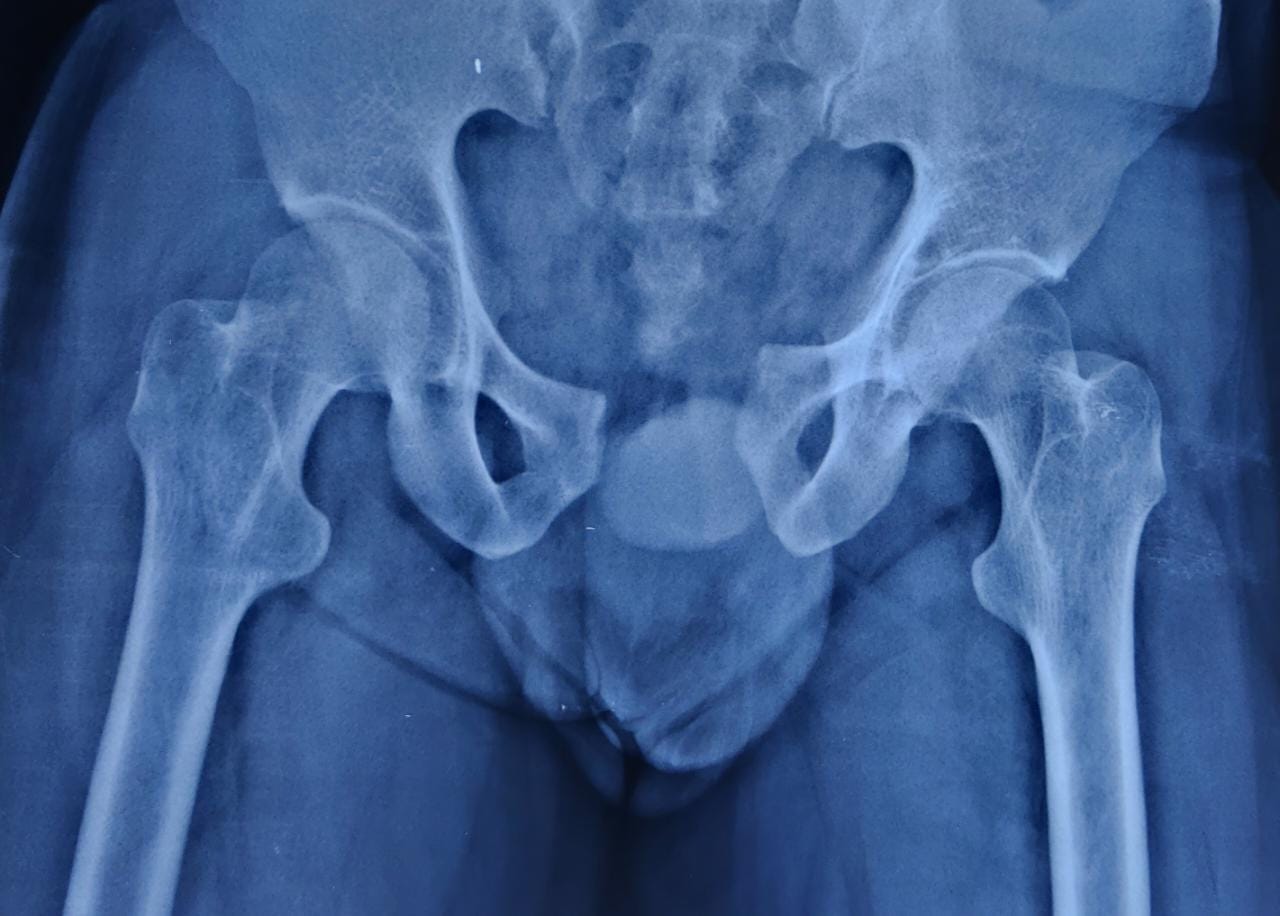

We as a tertiary care centre in the field of orthopaedics encounter a lot of complex trauma with extremely serious injuries around the hip

The injuries encompass hip dislocations with or without ACETABULAR fractures.

These fractures require urgent and precise surgical fixation to achieve the ultimate outcome. We at our centre routinely perform such surgeries.

Case 1